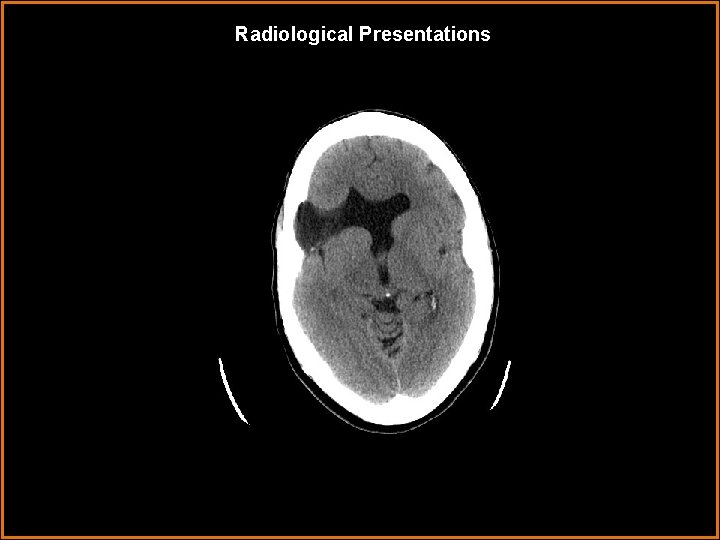

Case History 30 year old female with seizures and mental retardation.

Findings and Differentials Findings: A unilateral right frontal CSF filled cleft is identified. The cleft is in communication with the right frontal horn. The lining of the cleft demonstrates increased density consistent with gray matter. There is absence of the septum pellucidum. Differentials: • Schizencephaly • Porencephaly • Encephalomalacia • Arachnoid cyst

Diagnosis Open lip schizencephaly.